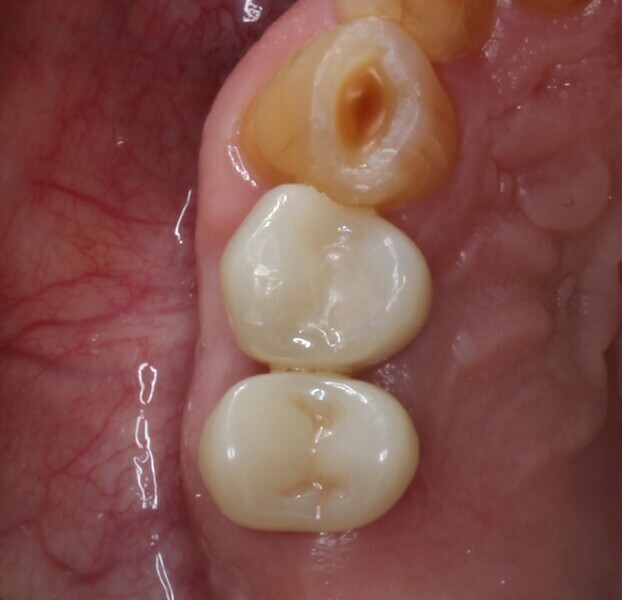

Fig. 22: Zirconia crowns in situ.

Fig. 23: Zirconia crowns in situ, occlusal aspect.

A waiting period of four months allowed adequate osseointegration of the implant (Fig. 20). The endodontic treatment of tooth #15 had been completed in the meantime, and the tooth had been prepared for a complete zirconia crown. Removal of the implant provisional restoration revealed a natural soft-tissue profile and an improved soft-tissue contour without the need for additional soft- or hard-tissue augmentation (Fig. 21).

Secondary impression was taken digitally with an intra-oral scanner and the relevant scan body. Definitive restorations were designed on exocad and milled in-house on CRAFT 5X (DOF) out of EVEREST Multilayer AT zirconia (Shade A3; UNC International). A deliberately lighter shade was chosen by the patient, as he intended to have the appearance of his other maxillary teeth improved. The implant crown was torqued in to 35 N cm, and the crown was cemented to tooth #15 using G-CEM ONE cement (GC Dental; Figs. 22–24).